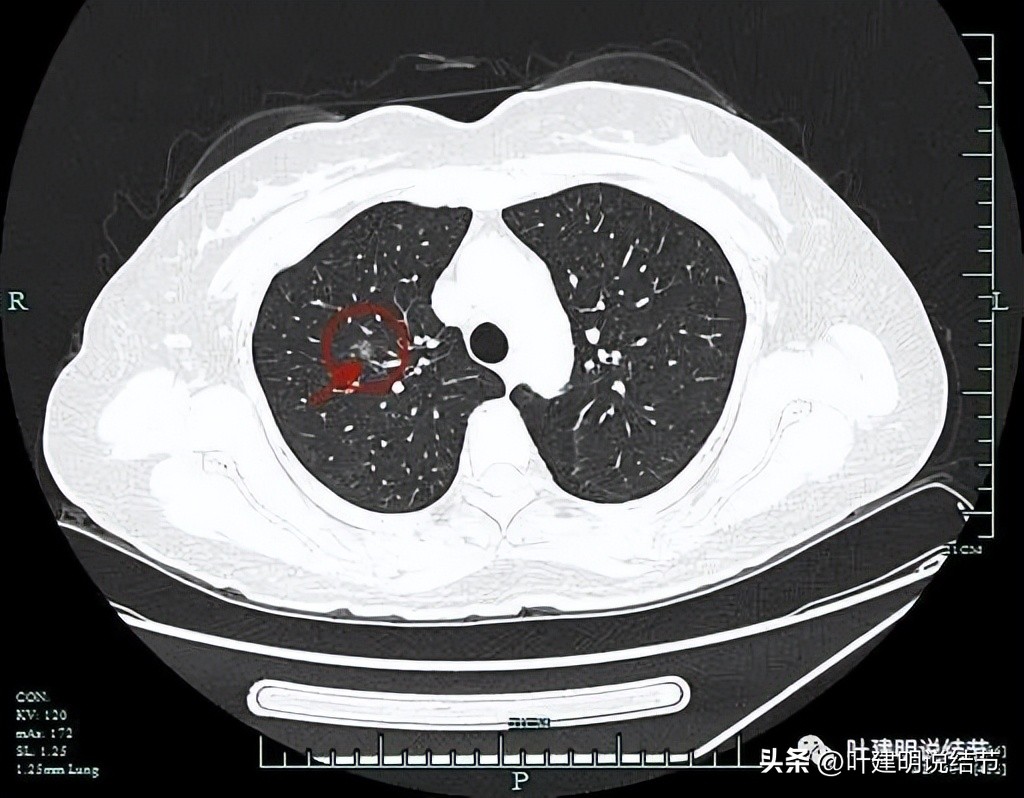

血管贴着病灶进入,并在灶内增粗比灶外还大,而且血管边缘毛糙。灶内有偏实性成分,边缘有毛刺,瘤肺边界清。是典型的混合磨玻璃结节,并有血管征与灶内血管异常增粗。

灶内血管蜘蛛网似的,而且僵硬增粗,病灶有分叶征,周围血管改变走行进入,病灶轮廓与边界清。这个样子更符合浸润性腺癌。

病灶毛刺明显,密度不均,灶内多处血管增粗,病灶表面分叶,整体轮廓与边界清。